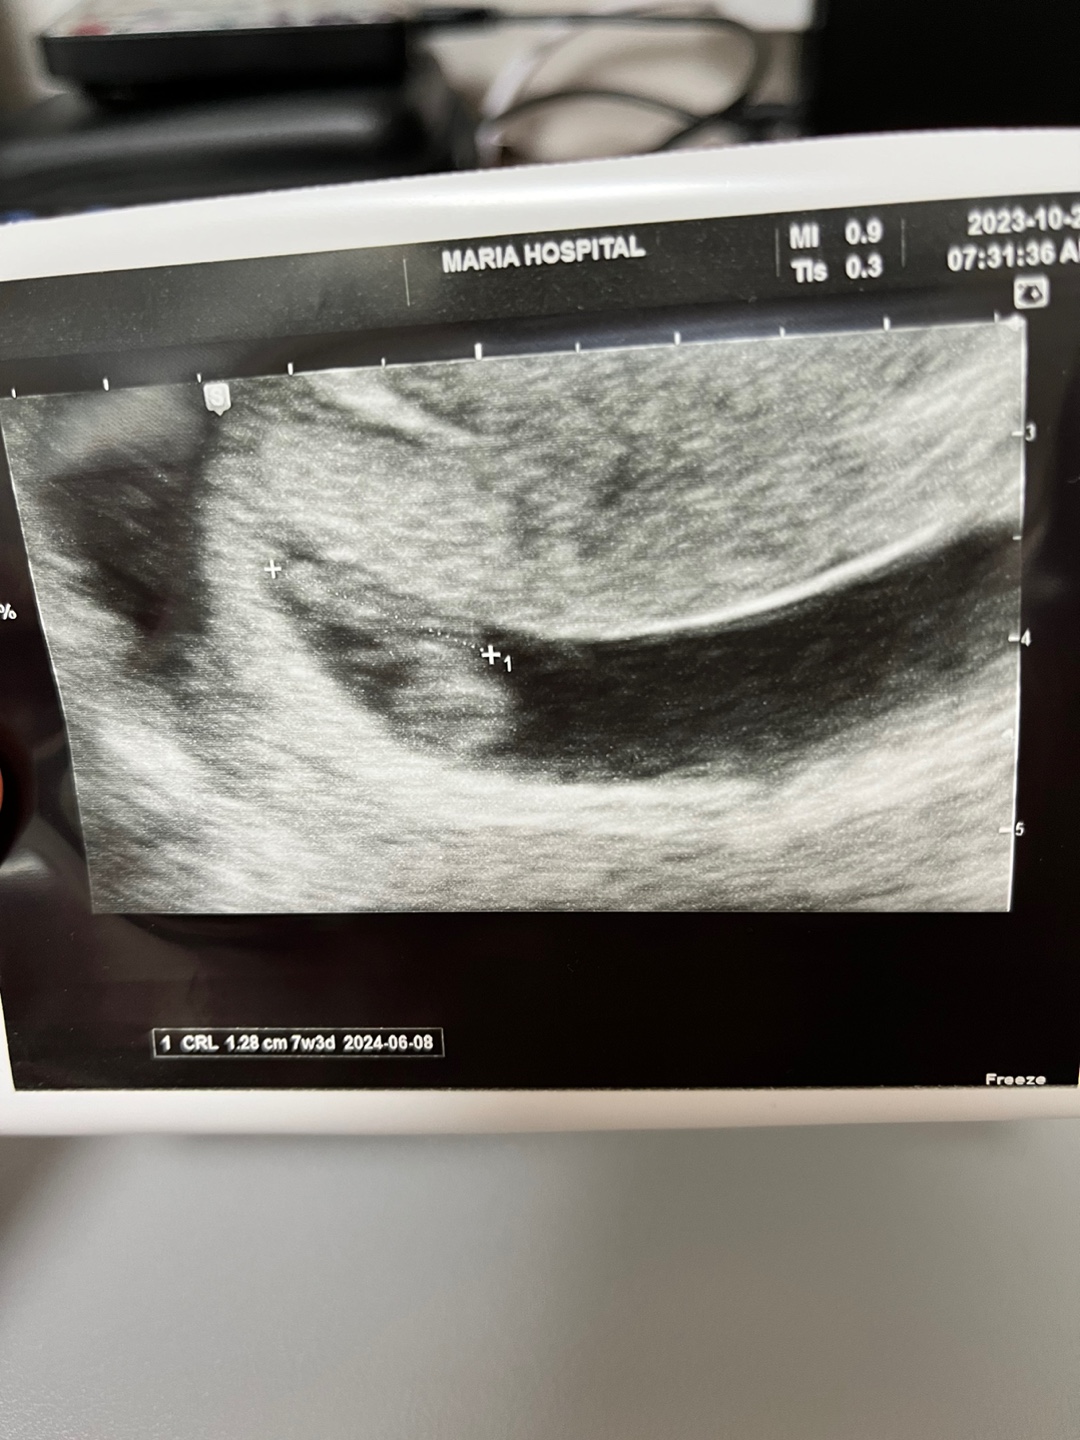

7주 3일, 1cm 넘었다!!!

심장소리 들은 이후 일주일이 지났다. 그 사이 갈색혈은 주사 두대로 멈췄고. 배 땡김과 화장실 가는 횟수가 너무 늘었다. 배 땡김은 지금 자궁이 확장되는 시기라 있을 수 있는 통증. 자궁이 확장되면서 방광이 눌리느라 화장실도 자주가게된다고 한다. 평상시에는 그나마 괜찮은데 자는도중에 새벽에 왔다갔다하려니.. 너무 귀찮고 중간에 잠이 계속 깨서 너무 피곤하고 힘들다. 어제도 4-5번은 간 거 같은데.... 훔.... 짜잔~~ 일주일새 커진 우리 럭키!! 드디어 1.28cm가 되었다!! 저번에는 모습이 잘 안보였었는데 이제 조금 컸다고 존재가 확실히 보인다. 밑에 동그란 부분은 난황(영양주머니)이고 윗부분에 길게 붙어있는 게 럭키. 언제쯤 젤리곰 모양의 럭키를 볼 수 있을까? 젤리곰 모양 너무 귀엽겠다~~~..

임신 2023.10.24